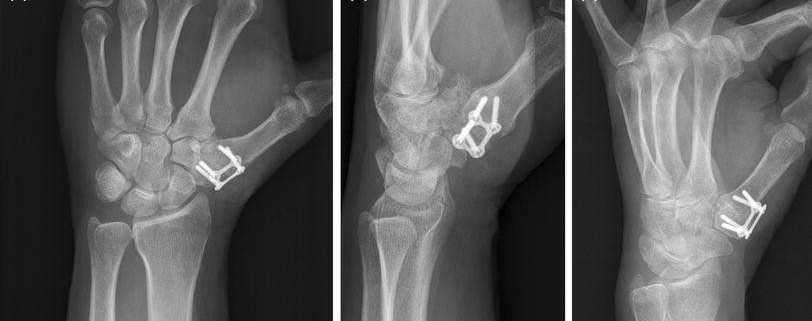

Thumb fusion surgery, also known as arthrodesis, is a procedure commonly used to treat severe, end-stage arthritis in the thumb. This surgery aims to eliminate the source of pain and restore function in the thumb by permanently fusing the bones in the thumb joint.

The diagnosis process typically involves a physical examination, discussion of symptoms and medical history. In most cases, diagnosis is confirmed via imaging tests like X-ray or MRI, which reveal the extent of damage to the thumb joint.